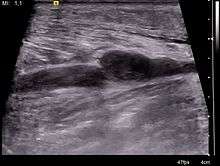

Additional images

Nerves, arteries and veins surround the gastrocnemius and soleus.

Muscle layer under the gastrocnemius

Cross section of the lower leg

Right femur. Posterior surface.

Back of left lower extremity.- Gastrocnemius muscle

- Gastrocnemius muscle

Lateral aspect of right leg.